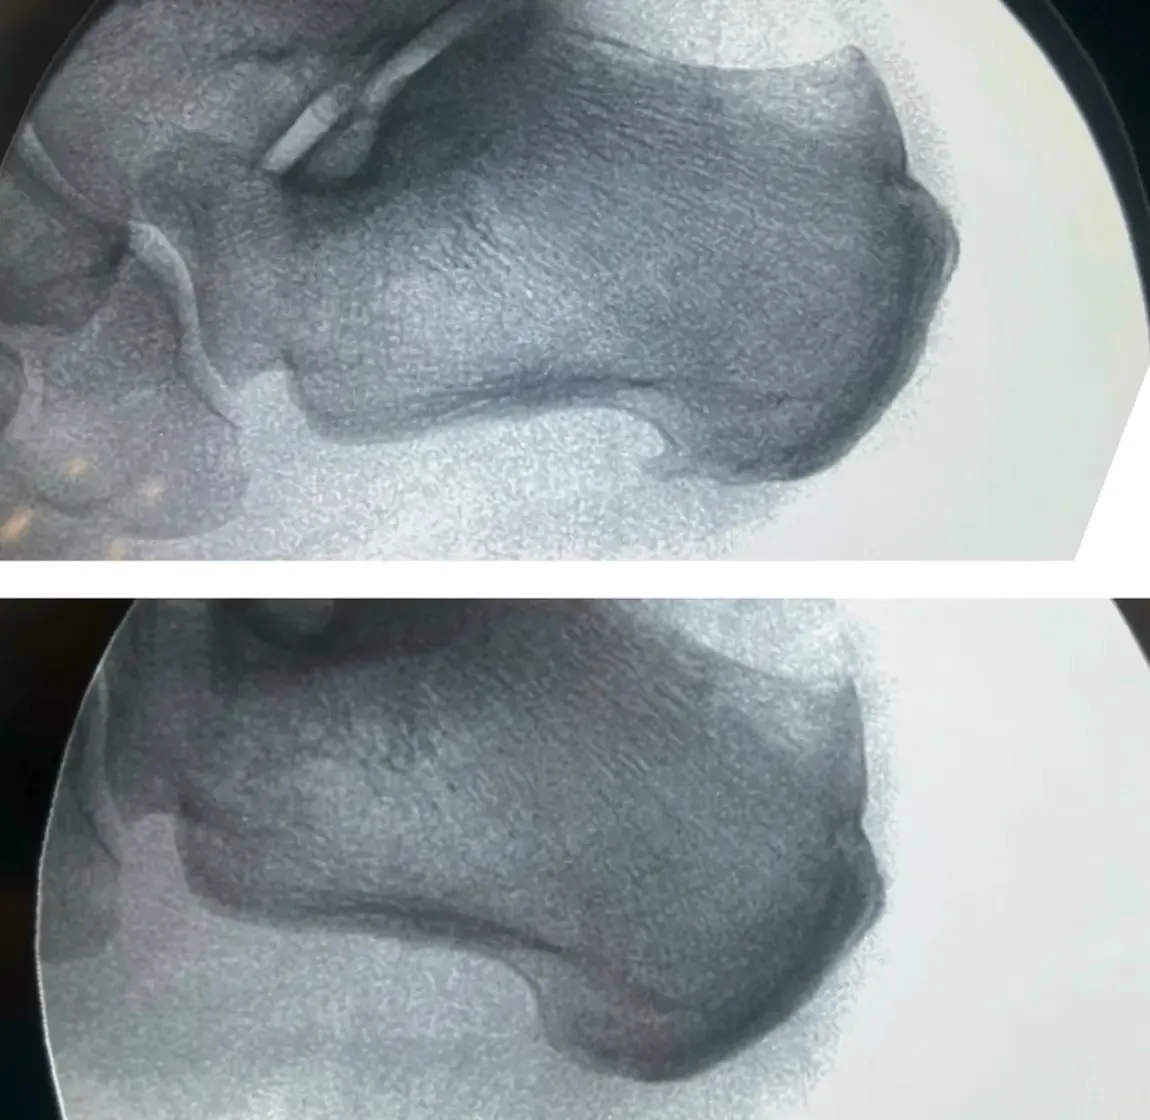

La Radiografía que lo Complicó Todo

Como muchos pacientes con dolor de talón, María acudió primero a otro profesional que le realizó una radiografía. Y ahí estaba: un espolón calcáneo visible como una pequeña espícula ósea.

Las radiografías muestran huesos, pero no pueden ver tejidos blandos como bursas o tendones. Por eso la ecografía podológica es fundamental en estos casos.

- El espolón calcáneo visible: presente, sí, pero sin signos inflamatorios alrededor, como un espectador silencioso

“¿Ve esta zona oscura, María? Esto es líquido inflamatorio en su bursa. Y aquí, el tendón de Aquiles muestra signos de sufrimiento. El espolón está ahí, pero no es el problema”.

¿Y el espolón? Seguía ahí, en su radiografía. Pero María ya ni se acordaba de él.